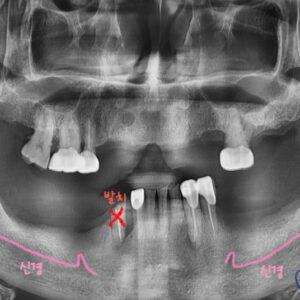

우선 치아의 뿌리와 치조골 및 전반적인 확인을 위해 파노라마 촬영을 시행합니다

파노라마 판독 결과

1번 치아 뿌리에 파절이 보이고

2번 치아에는 치조골 손상이 보이네요